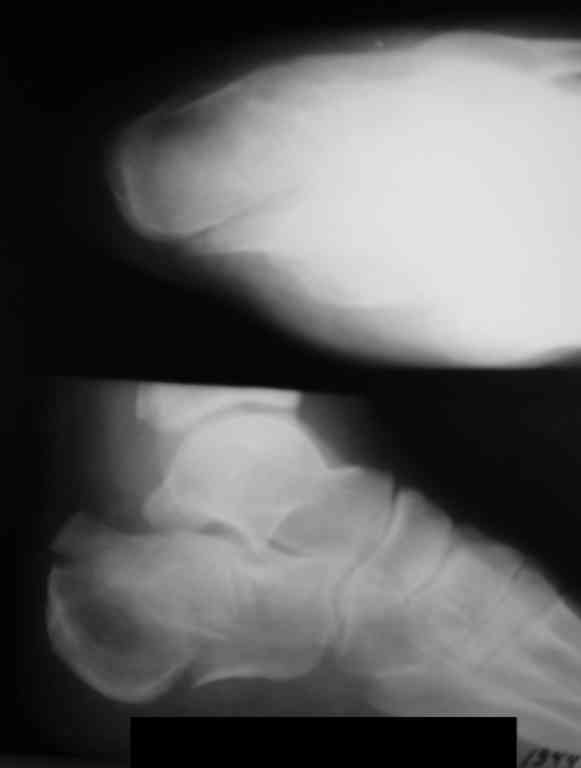

Если нет опыта в остеосинтезе пяточной пластиной то лучше начать с экскохлеации полости кистозного образования и заполнения его остеоиндукторами Коллапан, Тутопласт, etc.Закрытая репозиция с рентгенконтролем на столе и перкутанная фиксация спицами пяточного бугра с фиксацией в эквинусе могут дать вполне приемлемый результат.

Сустав похоже интактен, киста под вопросом,даже при наличии опыта остесинтеза пластиной, в данном случае выведение правильного угла и фиксация спицами более чем достаточно, да и намного спокойнее сон у хируга.

Вправление задней фасеты с восстановлением таранно-пяточного угла возможно минимально-инвазивным методом Essex-Lopresti - под ЭОП или графическим контролем введенной в пяточный бугор толстой спицей или стрежнем Штеймана, которые служат рычагом. Для удержания вводим несколько тонких спиц Киршнера, фиксация в эквинусе.Подробнее в Margo anterior 1-2 2000\издание АО Матис в России, на сайте www.mathys.ru в архиве есть все выпуски. Метод внедрен у нас с 2000 года и дает неплохие результаты.

Уважаемый Антон Андрианов. В отделении сочетанной травмы U,24 г Екатеринбурга также используется подобная методика. Предварительно делаем КТ. Предоперационное планирование возможности управления отломками. Мы выполяем репозицию шилом. Фиксацию крупных отломков спицами, а затем репозицию и фиксацию более мелких фрагментов. Кстати, на сайтеАО Матис Margo anterior 1-2 2000 - нет (почему-то?). Было бы интересно узнать как и куда вы вводите спицы.

Действительно архив Margo Anterior начинается с 2001 года.Но я могу эту статью по лечению переломов пяточной кости,очень обстоятельную, санировать и выслать мылом на ваш адрес или разместить на rapidshare ru и указать ссылку на форуме. несколько тонких спиц вводятся в разных направляениях при многофрагментарных переломах иногда через подтаранный сустав для удержания репозиции. Их и стержень удалем через 6 недель.